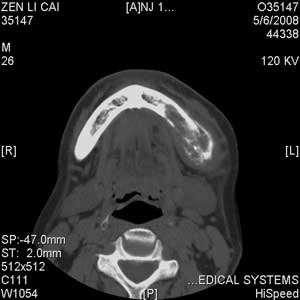

以下是引用jiangjing在2008-5-28 15:56:00的发言:[br]下颌骨左侧部骨质破坏,轻度膨胀,瘤骨形成,软组织肿胀考虑 恶性骨肿瘤-----肉瘤类